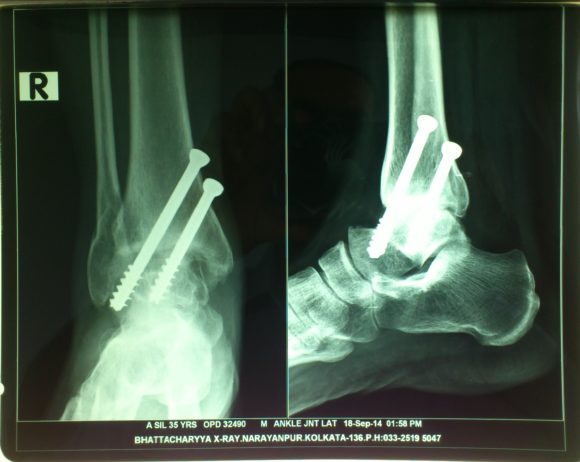

Arthroscopic Ankle Fusion

Ankle Arthrodesis fuses the bones of the joint completely, making one continuous bone out of two bones. The goal is to reduce pain by eliminating motion in the arthritic joint. During arthrodesis, your surgeon removes the damaged cartilage and then uses screws to fix the joint in a permanent position. Over time, the bones fuse or grow together, just like two ends of a broken bone grow together as it heals. By removing the joint, the pain disappears.

This surgery was earlier done by open methods with a high complication rate. Arthroscopy specialists prefer to do it with arthroscopic techniques, minimizing complications and optimizing the results. With sophisticated arthroscopic techniques we have successfully fused ankles with 5 mm keyholes – even in cases which had 5-6 previous unsuccessful open surgeries and big scars!!

xray picture of arthroscopic ankle arthrodesis